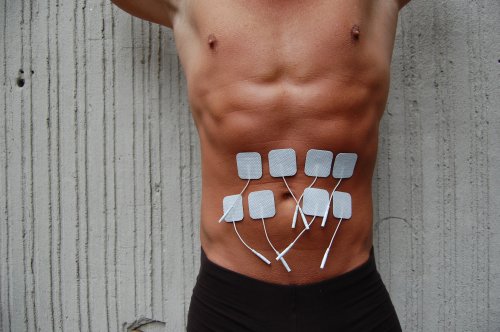

- Pulse Based Stimulation: Here a device specifically made for stimulating the body is used. Common examples are TENS and EMS units as well as a few devices sold for erotic purposes. These devices all output a pulse type waveform that is designed to safely stimulate muscles and nerves. This is arguably the safest form of electrostimulation.

As stated in Section 3, pulse type devices are by far the best choice erotic play. The safest and perhaps best all around device is the battery powered TENS unit. TENS stands for Transcutaneous Electrical Nerve Stimulation and was developed by the medical community for therapeutic purposes. These devices generally output a pulse type waveform that is adjustable in current (level or amplitude), pulse width (energy) and frequency (rate). The more advanced (and expensive) devices offer a few different modulation options to vary the output. Nearly all TENS units are limited to a maximum output of 80ma (which is 0.08 amps) and have a bipolar output. This is enough current for most electrostimulation needs but more advanced practitioners may desire more (especially for anal or vaginal stimulation in S&M scenes). TENS units are available from several sources and usually start around a few hundred dollars. They typically offer two isolated channels so you can wire up two different areas of the body at once and independently adjust the level to each.

Finally, the pads that come with most TENS units and the smaller EMS pads are also very useful. These can be attached to the genitals, buttocks, inner thighs and other interesting areas. Remember if you want to feel the sensation equally in both electrodes, they should be the same size and in similar locations on the body. Also, keep in the mind the path the current will take. It can often be felt all along the path and not just at each electrode site. This is why the inner thighs, for example, can be interesting. Also, various muscles can be stimulated if desired.

Finally, the pads that come with most TENS units and the smaller EMS pads are also very useful. These can be attached to the genitals, buttocks, inner thighs and other interesting areas. Remember if you want to feel the sensation equally in both electrodes, they should be the same size and in similar locations on the body. Also, keep in the mind the path the current will take. It can often be felt all along the path and not just at each electrode site. This is why the inner thighs, for example, can be interesting. Also, various muscles can be stimulated if desired.